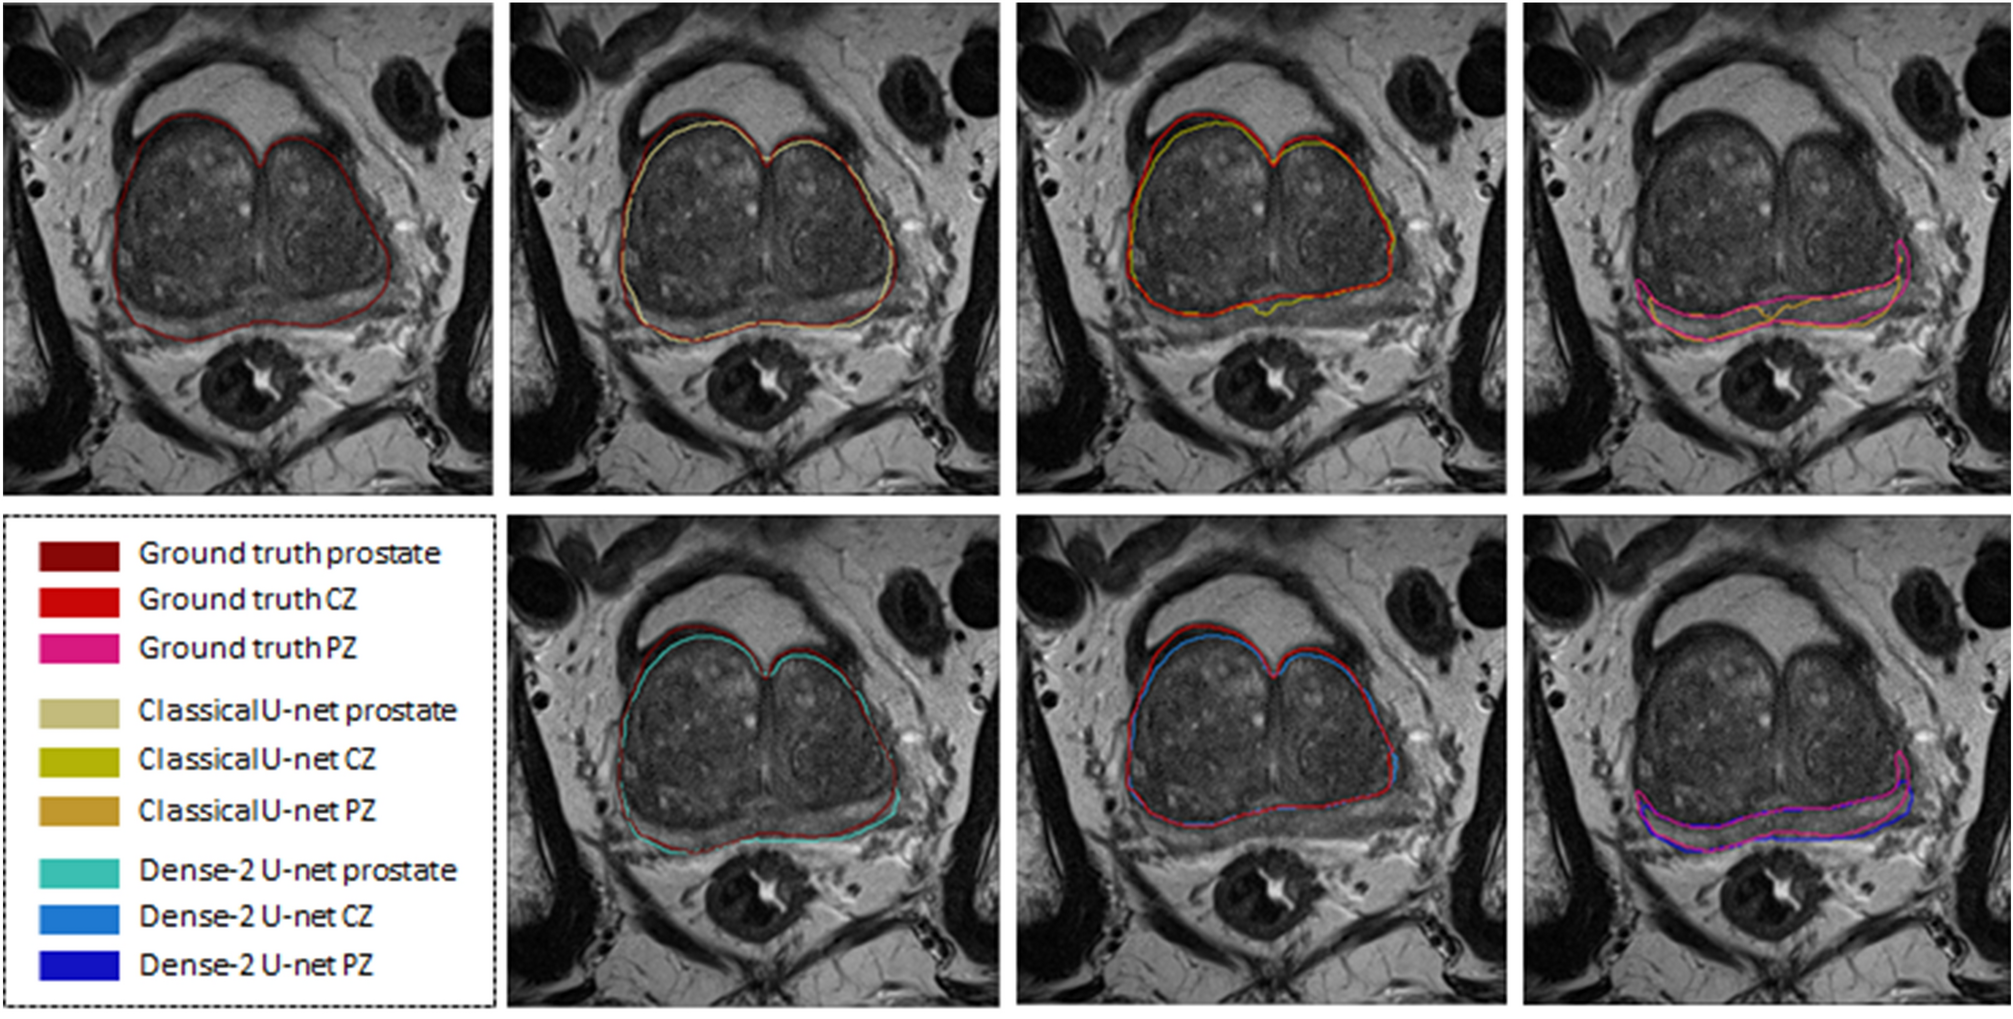

Figure 2

Segmentation results of the classical (first row) and Dense-2 U-net (second row) algorithms. From left to right, ground truth, prostate, CZ and PZ.